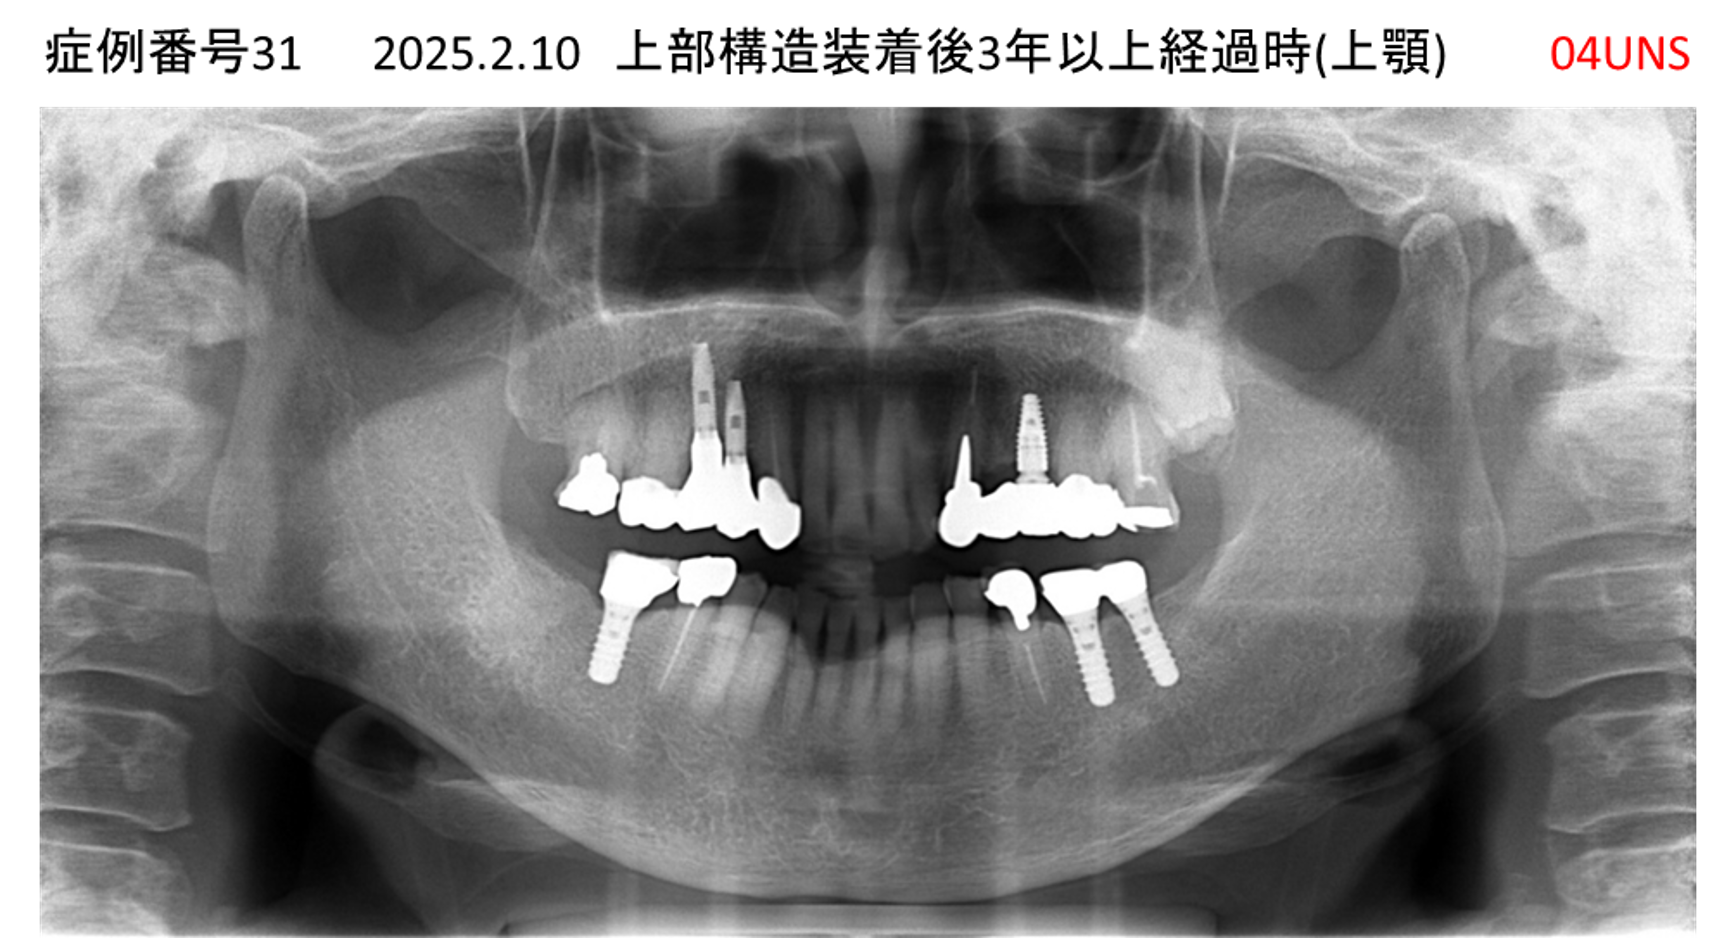

かめない/上の歯が揺れてきた患者様のインプラント症例

| 治療名称 |

インプラント |

| 治療費用 |

390万円+税 |

| 治療期間 |

6か月 |

| 患者さんの症状(主訴) |

かめない。上の歯が揺れてきた。 |

| 治療内容 |

サイナスリフト、抜歯即時インプラント |

| 治療結果 |

上の歯の揺れが収まった。噛めるようになった。食事がおいしい。 |

| 治療の注意点(リスク/副作用) |

インプラントが壊れたら再治療が必要 |